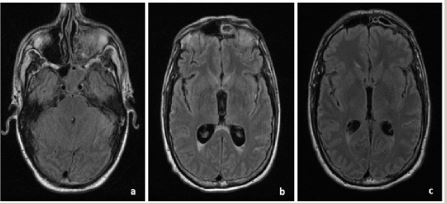

뇌수막염

뇌수막염은 장마철의 습한 환경에서 세균 또는 바이러스에 의해 발생하는 중증 감염입니다. 이 질병은 두통, 높은 체온, 경련, 피부발진 등의 증상을 유발할 수 있습니다.

뇌수막염은 급성 상태로 응급 치료가 필요합니다.